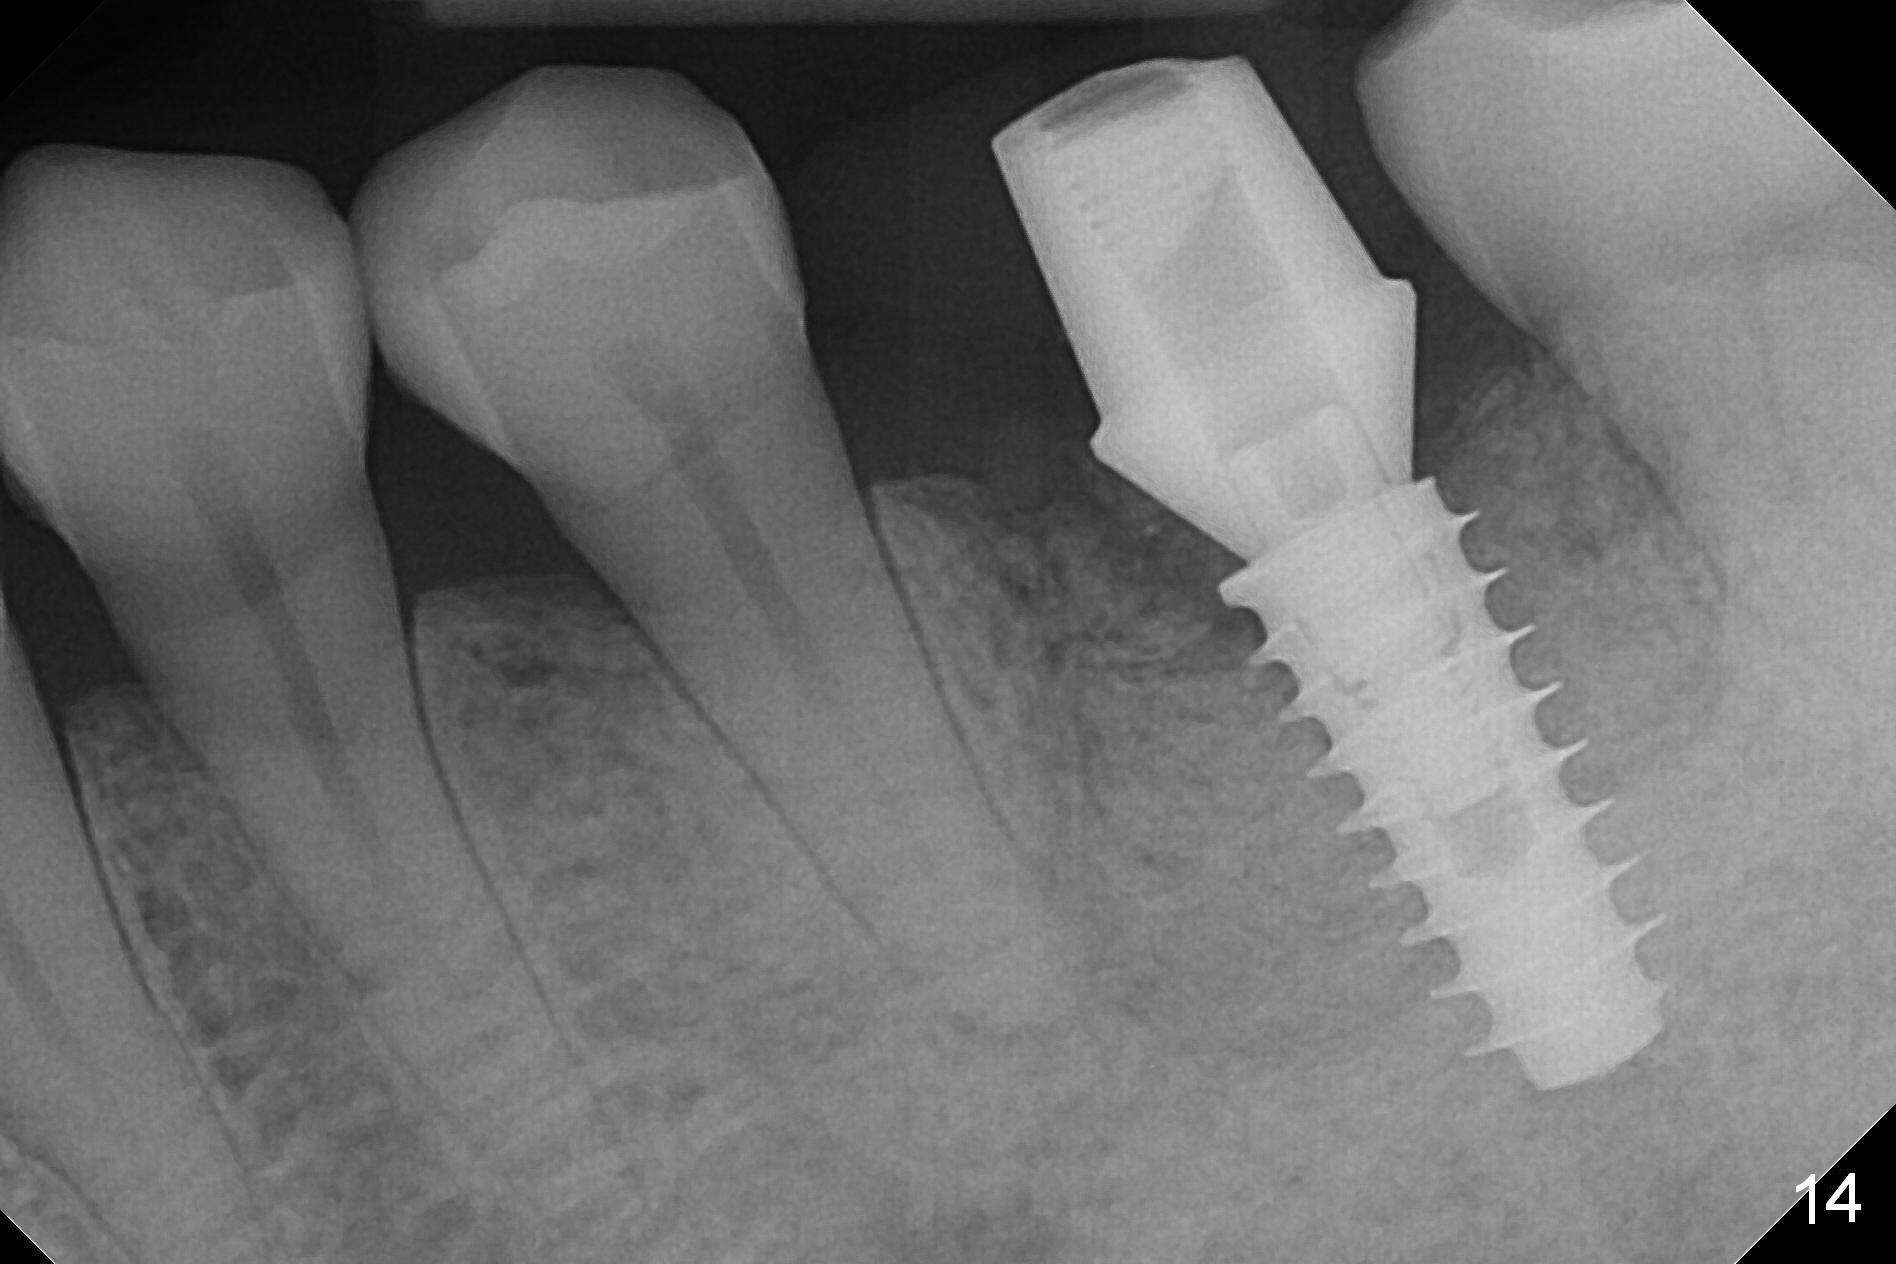

There is a new pattern of bony trabeculae around the implant 4.5 months postop (Fig.14). Bone density increases 1 year 4 months post cementation (Fig.15).